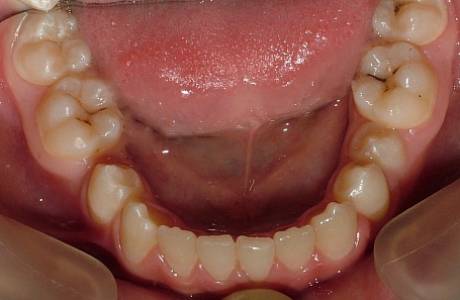

После лечения

Прикус восстановлен, зубы выровнены.